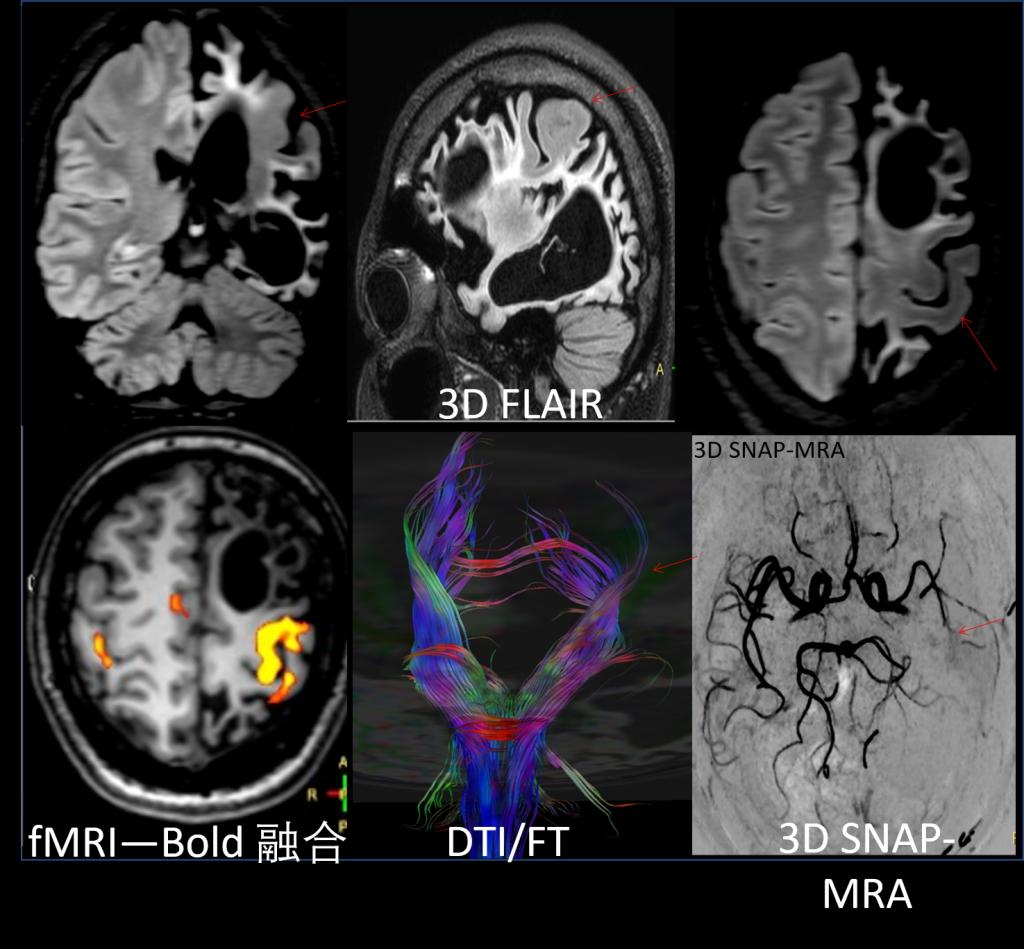

中心的研究团队包括多名医学影像领域的著名科学家和青年骨干,以医学成像和临床应用研究为核心,推动其在中国的发展,并在科技创新、产业结合方面提供多学科全球化的科研、教学和临床服务。影像中心拥有两台先进的3T全身磁共振成像系统(Philips Ingenia CX 3.0T和Siemens Prisma 3.0T),一台超高场5T全身磁共振成像系统(联影 Jupiter 5.0T),多套超声成像系统(含一台ICONEUS 脑功能超声成像系统),以及配套的成像技术、软硬件开发平台、图像数据处理工具和临床图像处理软件。中心的专业运行和技术支持团队以磁共振平台为核心,面向用户提供优秀的基础科学研究、成像技术研发和临床医学转化服务。

影像中心自成立以来,承担了科技部、国家自然科学基金委、卫生部、北京市科委等近百项国家和省部级项目,收到各种研究经费支持达5000万余元,已发表论文600余篇,发明专利60余项,国际专利10余项,培养学生130余人,获得各种奖励30余项。影像中心已成为全球重要的医学影像尤其是磁共振技术研发中心,开发出大视野高分辨血管壁多对比度成像、三维心肌定量成像、定量血流成像、定量生理成像、无变形高分辨率弥散成像等诸多原创技术,同时这些技术被广泛地应用在多项大规模临床人群队列研究当中形成了针对心脑血管、神经变性性疾病等原创性影像学解决方案。